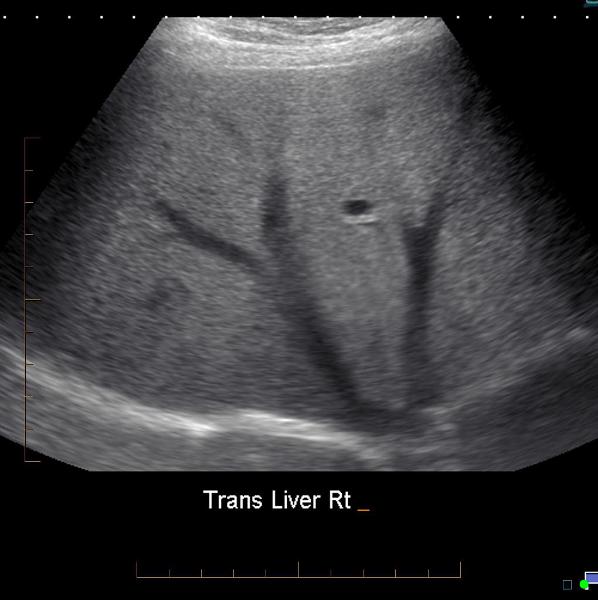

Explain the Transverse plane for the liver exam.

The transducer should be angled in a steep cephalic direction to be as parallel to the diaphragm as possible. The transverse plan allows images of liver parenchyma, vascularity and ductal structures.

Transverse

Right lobe W/ hepatic

veins, IVC

Right lobe W/ dome

Right lobe W/ portal

veins

Right lobe W/ kidney and gallbladder